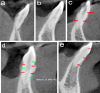

(a) Vertucci’s Type-I, Ahmed’s 1MI1 (b) Vertucci’s Type-III, Ahmed’s 1MI1-2-1 (c) Vertucci’s Type-V, Ahmed’s 1MI1-2 (d) Vertucci’s Type-VII, Ahmed’s 1MI1-2-1-2 (e) Not classified by Vertucci, Ahmed’s 1MI1-2-1-2-1.